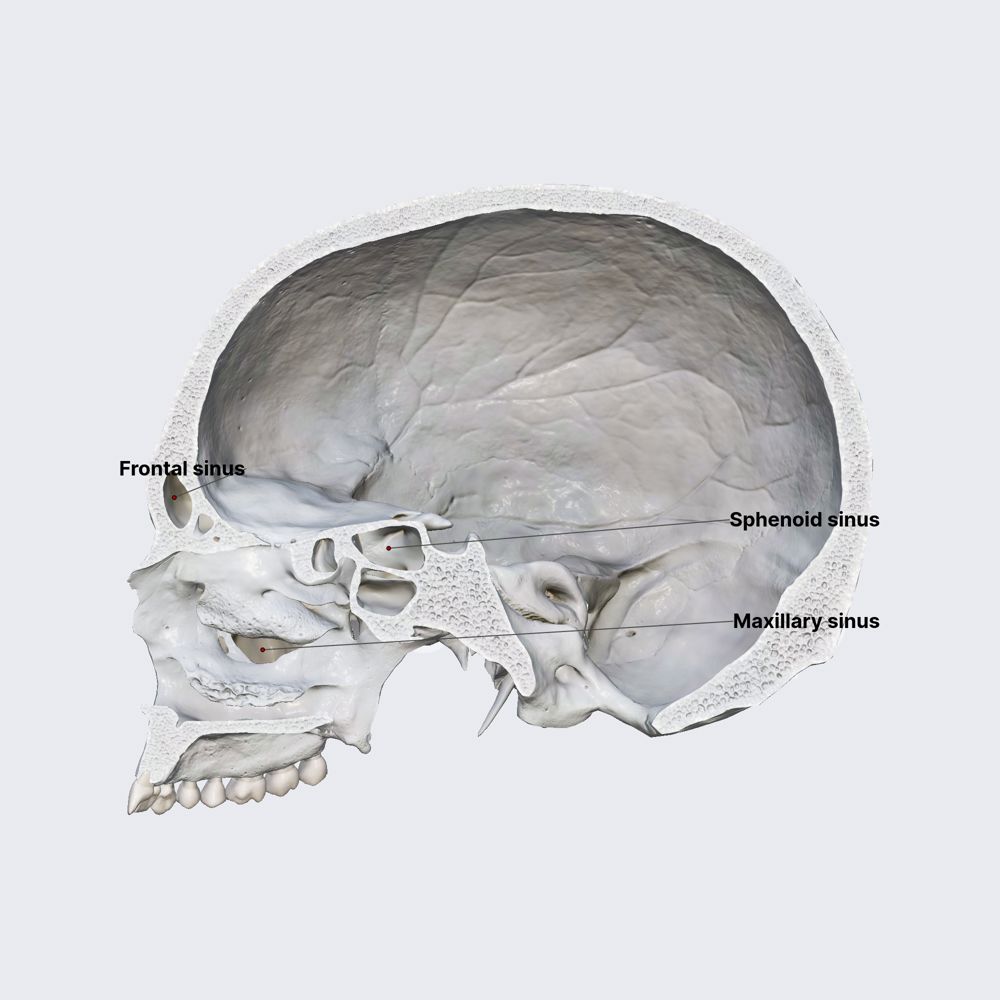

- Paranasal sinuses

- Maxillary sinus

- Frontal sinus

- Sphenoid sinus